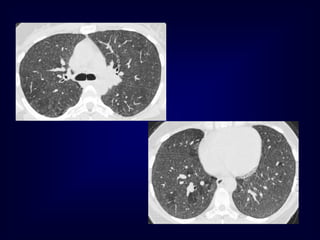

Langerhans Cell Histiocytosis HRCTFindings Small peribronchiolar nodules (1-5mm) Thin-walled cysts (< 1cm), Bizarre and confluent Ground glass opacities Late signs: irreversible / parenchymal fibrosis Honey comb lung, septal thickening, bronchiectasis

• 134.

Langerhans Cell Histiocytosis 1year later Peribronchiolar Nodules Cavitating nodules and cysts

Langerhans Cell Histiozytosis KeyFeatures Upper lobe predominance Combination of cysts and noduli Characteristic stages Increased Lung volume Sparing of costophrenic angle S M O K I N G